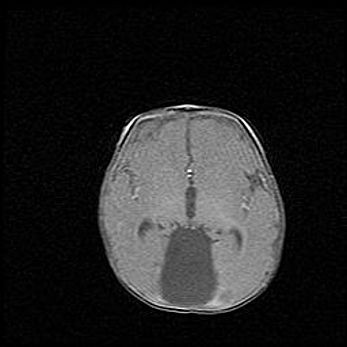

Мальформация Денди-Уокера. Киста задней черепной ямки.

Агенезия мозолистого тела.

Возраст: 2,5 месяца

Вес: 2420 г

Пол: женский

Окружность головы: 37 см

Срок гестации: 32 недели

Мальформация Денди—Уокера — редкий вид патологии ЦНС, представляющий собой врожденный порок развития каудального отдела ствола и червя мозжечка, ведущий к неполному раскрытию срединной (Мажанди) и латеральных (Лушка) апертур IV желудочка мозга. Для этогно синдрома характерна триада симптомов: гипотрофия червя мозжечка и/или полушарий мозжечка, кисты задней черепной ямки, гидроцефалия различной степени. В 70% случаев порок сочетается и с другими аномалиями головного мозга, в частности с агенезией мозолистого тела.